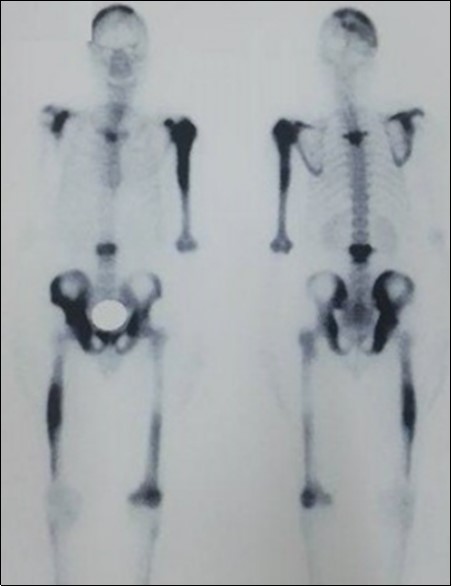

We report the case of an asymptomatic 49 years old male patient, in which a routine check objectified a biological cholestasis (gammagmutamytransferase = 2-3N and ALP = 5-6 N without hyperbilirubinemia or cytolysis). Nos past medical facts were noted. Abdominal ultrasound, viral markers and antibodies measurement (Ac Anti-nuclear, anti-Mitochondrial, anti-LKM1, Anti-cytoplasmic) were normal. Magnetic resonance choalngiopancreatography objectified multiple biliary strictures and parietal irregularities evocative of SC (Figure 1). Colonoscopy showed no associated inflammatory bowel disease. Patient received high doses of ursodeoxycholic acid (20mg/kg) for the SC with partial improvement of liver function but persistence of a marked rise in ALP level. In order to better characterize the nature of ALP, a dosage of ALP isoenzymes was performed and objectified a predominant bone fraction (83%), while liver fractions H1 and H2 were respectively of 12% and 4%. X rays objectified bone condensations with a fibrillar appearance and bone hypertrophy suggestive of PD (Figure 2). A bone scan made for lesions mapping showed a multifocal PD (Figure 3). The patient was treated by bisphosphonates (injections of zoledronic acid), which was associated with a decreasing in ALP level after 6 months.

Figure 3.Bone scan mapping lesions showing a multifocal achievement of the bones